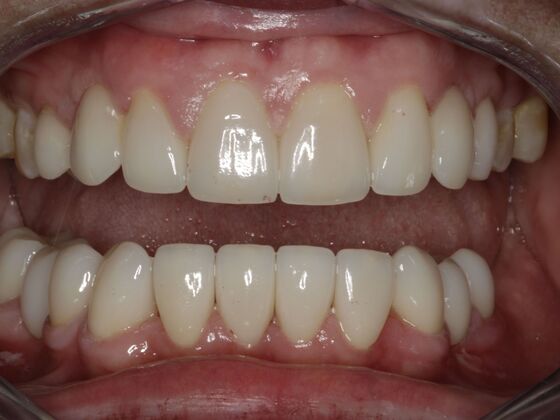

Smile Makeover & Veneers: Case 19

This may be one of the most difficult, yet rewarding cases I have ever done. A combination of meds for seizures and poor oral hygiene led to this painful, infected condition. She would not smile, talk to people, and was embarrassed. We thoroughly cleaned her teeth and performed laser, NON-surgical recontouring of her gums, removed several teeth and placed crowns, bridges and veneers to reach this end product. An amazing transformation that truly changed her life.